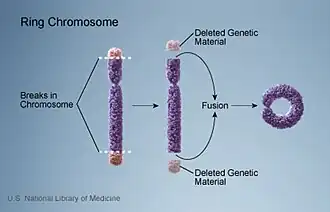

| Diagram of the formation of a ring chromosome | |

All chromosomes have the capacity to form ring chromosomes. The symptoms and severity largely depend on the amount and location of the genetic information lost.[2] If the ends of the chromosome fuse with no loss of genetic material, the individual retains the normal phenotype with relatively slight differences. However, evidence suggests that when there is deletion of genetic information at the distal unstable ends where the subtelomeric structures fuse, syndromes associated with that particular chromosome arise.[3]

There are two proposed mechanisms of forming the ring chromosome. One suggests that chromosome 15 undergoes distortion on both p and q arms prior to the fusion of two broken arms, resulting in great loss of genetic materials. Therefore, the patients of this type of ring chromosome 15 display severe clinical features.[12]

The other proposed mechanism suggests the direct fusion of two telomeres without losing any of the telomeric and subtelomeric sequences. Consequently, most of the genetic material is conserved and symptoms are expressed in a milder form, making diagnosis more difficult.[13]